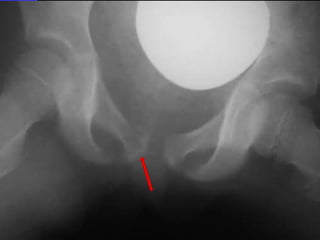

Radiographs of pelvis and hips were obtained

R

Salter Harris I

Case-3 A 5-y-oldmale tripped and fell down the last 4 stairs. He went on to play basketball with no pain. At home he complained of right hip pain. At night he woke up C/O of right hip pain. Taken to ER , he had normal ROM of his extremities including the right leg. However when he moved it, he said it did hurt. Radiographs of pelvis and hips were obtained

• 105.